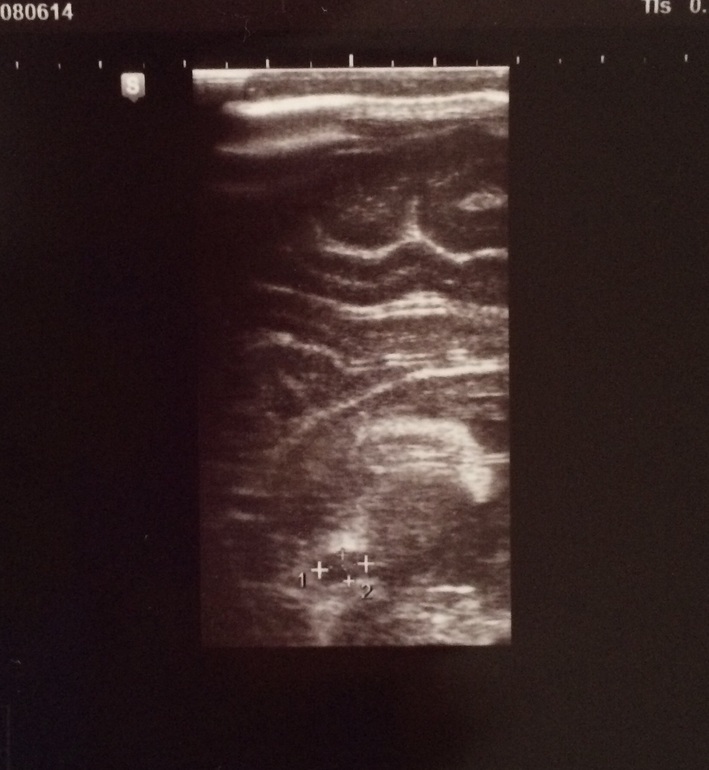

НСГ в 4.5 мес. Мамское сердце неспокойно

Посещение врачаПривет, дорогие! У мелочи в мозгу нашли локальное расширение в 6 мм, похожее на кисту.

Вот:

Наша педиатр, современная компетентная врач, говорит не переживать и просто контролировать через 3 мес. и 6 мес. от этого УЗИ. Главное, чтоб не было прогресса. На вопрос, откуда это идет, ответила, в 80% -- от перенесенной мамой инфекции во время беременности. Я всю беременность отскакала как конь без единого ОРВИ, и только в 17 недель был у меня герпес на губе, который благополучно залечила Зовираксом за неделю. Герпес периодический всю жизнь. Скрининги никаких отклонений в голове ребенка не нашли, узист грамотный, проглядеть не мог. У невролога в 3 мес. к ребенку серьезных претензий нет, кроме небольшого плечевого зажима, развитие в срок. Короче, клинических проявлений это образование не дает.